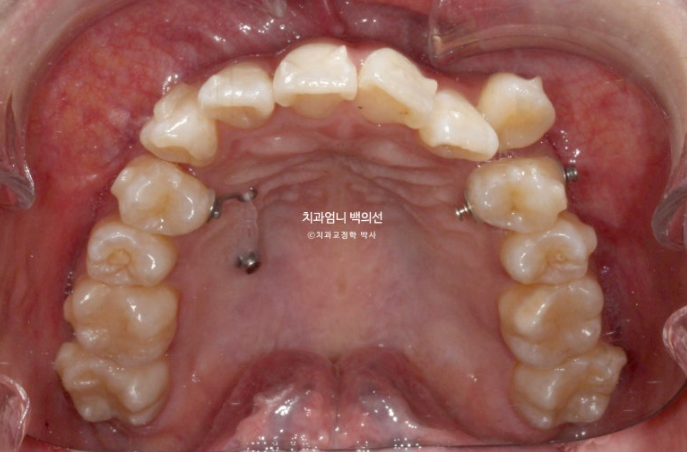

24년 11월 드디어 66개 장치를 모두 낀 후 모습입니다.

24.11

덧니는 제자리를 찾았고 아직 중심선 불일치가 보입니다.

덧니가 해결되었으니 큰 공사는 끝났네요.

어금니 교합이 뜨는 부분과 먼저 닿는 부분들을 개선하고자 재제작에 들어갑니다.

재제작 추가장치 갯수는 17개 나왔습니다.

어금니 교합 안정화와 중심선 개선을 위해 추가장치에서는 고무줄 처방이 들어갑니다.